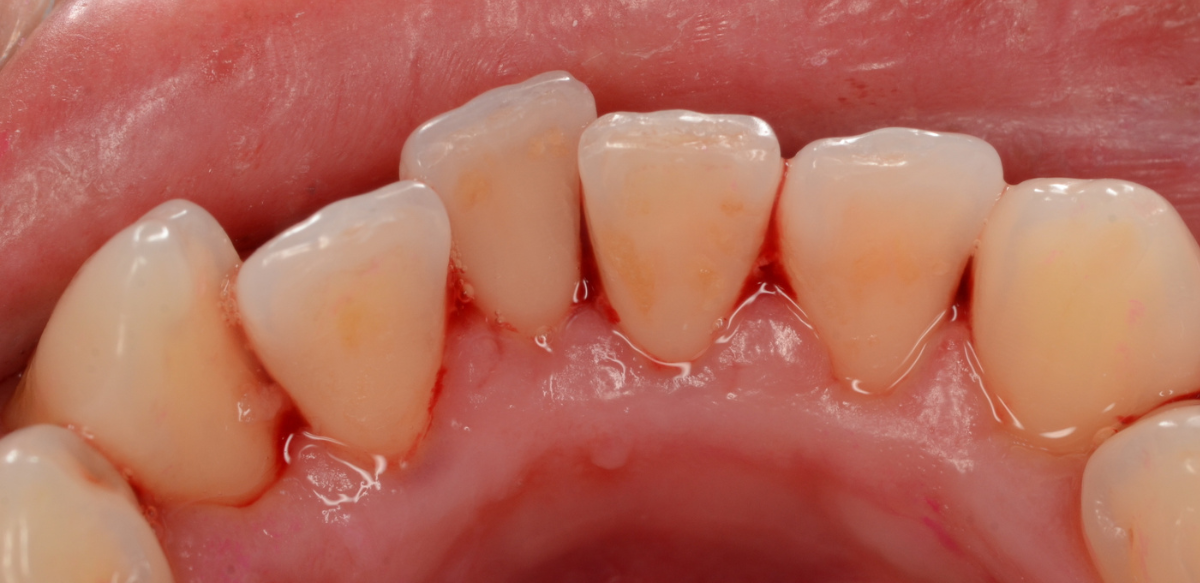

Case.3 縁下歯石除去後、3か月の状況

今回は、下の前歯の縁下歯石を除去した後、3か月後のメンテナンスにいらっしゃった方の治療前後です。

前側から見た所です。

とても綺麗に歯肉が治っているのがわかると思います。

歯石除去が終わったあとも、頑張ってお手入れしているのがうかがえます。

歯石除去だけでは、ここまで綺麗には治りません。

裏側の歯肉の状態も大きく変わりました。

年齢もお若い方なので、歯肉の回復も早いです。

ある程度まで歯周病が進行してしまいますと、完全に歯肉が元に戻るのは難しくなってしまいます。

本格的な歯周病になる前に治療を受けていただけて、本当に良かったと思います。

あとは、油断せずに持続していただきたいと思っています。